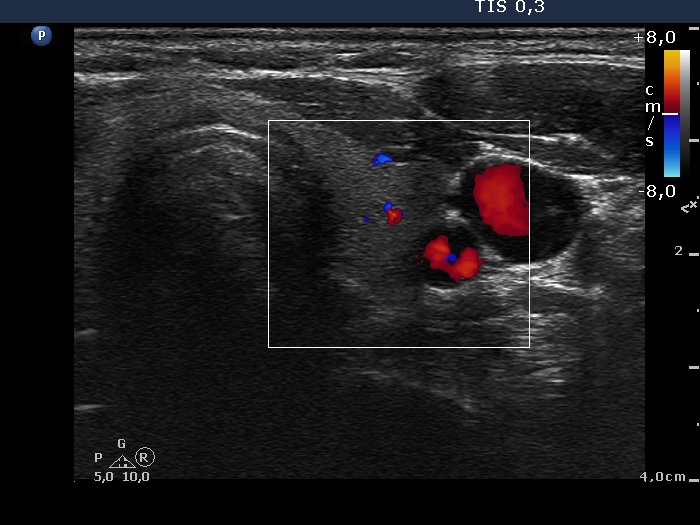

Follow-up examination 4 months after initial investigation (third row of images):

Clinical presentation: The inflammatory complaints of the patient suddenly stopped within 24 hours of the steroid intake and did not recur after discontinuation of the steroid.

Palpation: no abnormality.

Functional state: subclinical hypothyroidism with TSH-level 4.92 mIU/L, FT4 13.7 pM/L. Erythrocyte sedimentation rate was 11 mm/H, CRP was 0,9 mg/L.

Ultrasonography. The thyroid became smaller and the echo structure had normalized. Nevertheless, there were several minimally-moderately hypoechogenic areas in both lobes. There were no significant changes in the vascularization.